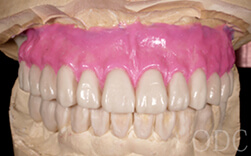

上部構造

インプラント治療を成功に導く為に必要不可欠な歯科技工。インプラント補綴は、特に技工士の技術が重要となる。オールオン4において、“口の中の見える部分”は全て歯科技工士の仕事なのです。当医院のオールオン4補綴はインプラント補綴で有名なノーベルバイオケア社公認インストラクター 志田和浩氏によるものです。本症例は、1歯1歯プロセラを装着した、オールオン4の上部構造としては最高級のものの一つです。